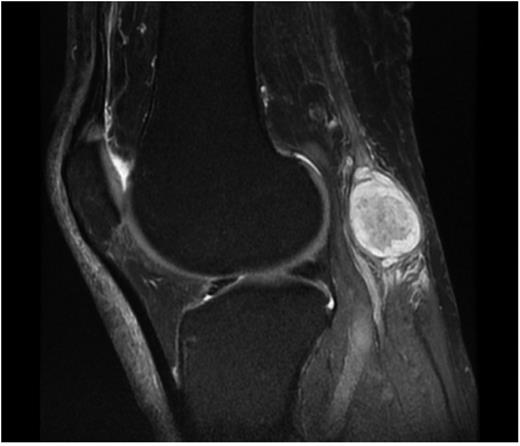

Fifty-eight-year-old man presented to the outpatient clinic of orthopaedics department with the complaints of slowly growing mass on his right popliteal region and mild pain and intermittent paresthesia of right leg and right foot. The patient emphasized that the mass existed for 2 years but has grown in the last 6 months. On physical examination, 4 × 2 cm mobile, solid mass was palpable at the posterior of the knee. There was no erythema, warmth or ulceration and Tinel's sign was positive. Sensory and motor examinations of lower extremity were normal. Ultrasound imaging showed that the mass was solid and separate from the adjacent muscles and tendons. MRI showed well-defined solid, heterogenous, dense mass originating from the tibial nerve (Fig. 1). Surgical exploration and excisional biopsy was performed. At prone position with longitudinal incision, popliteal region was explorated and tumoural mass originating from tibial nerve was dissected. Sheath of the nerve was incised longitudinally to minimize damage to the nerve fascicles and the mass was resected in en-bloc form by sharp dissection using the microscope with no complication. The patient was discharged at the post-op third day. At the third week of the operation, the patient was free of all complaints. Histopathological examination of the mass revealed hypocellular Antoni B and spindle-shaped Schwann cells containing Antoni A areas with nuclear palisading. Also immunohistochemical staining (S100+) confirmed the diagnosis of schwannoma.